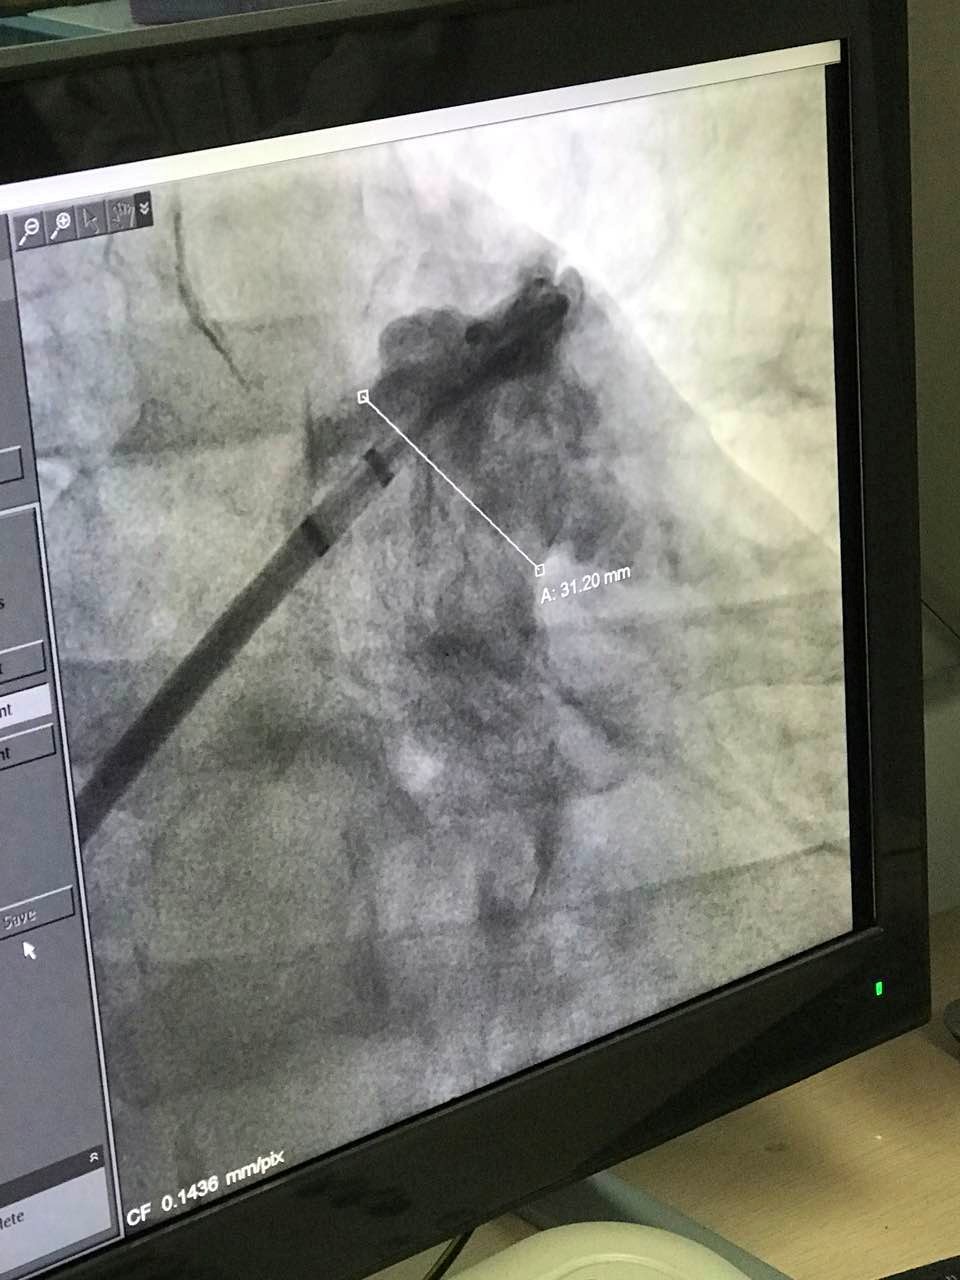

接受手术的患者为一名63岁男性,被诊断为心律变态,其心房纤颤伴有急剧心室率,心职能为2级。经食路超声丈量患者左心耳开口直径为31.2mm,左心耳深度约为10mm,为鸡翅型心耳结构。因患者左心耳开口大,深度浅,拥有丰硕临床经验的武汉大学人民医院心血管内科黄鹤主任和来自香港的林逸贤医生选用型号为3640的LAmbre?左心耳封堵器对患者执行封堵,用时不到40分钟便顺利实现整个手术。LAmbre?型号为3640的左心耳封堵器为目前已上市的尺寸最大的左心耳封堵器,为大心耳的患者提供了安全有效的手术解决规划。

图:术中造影